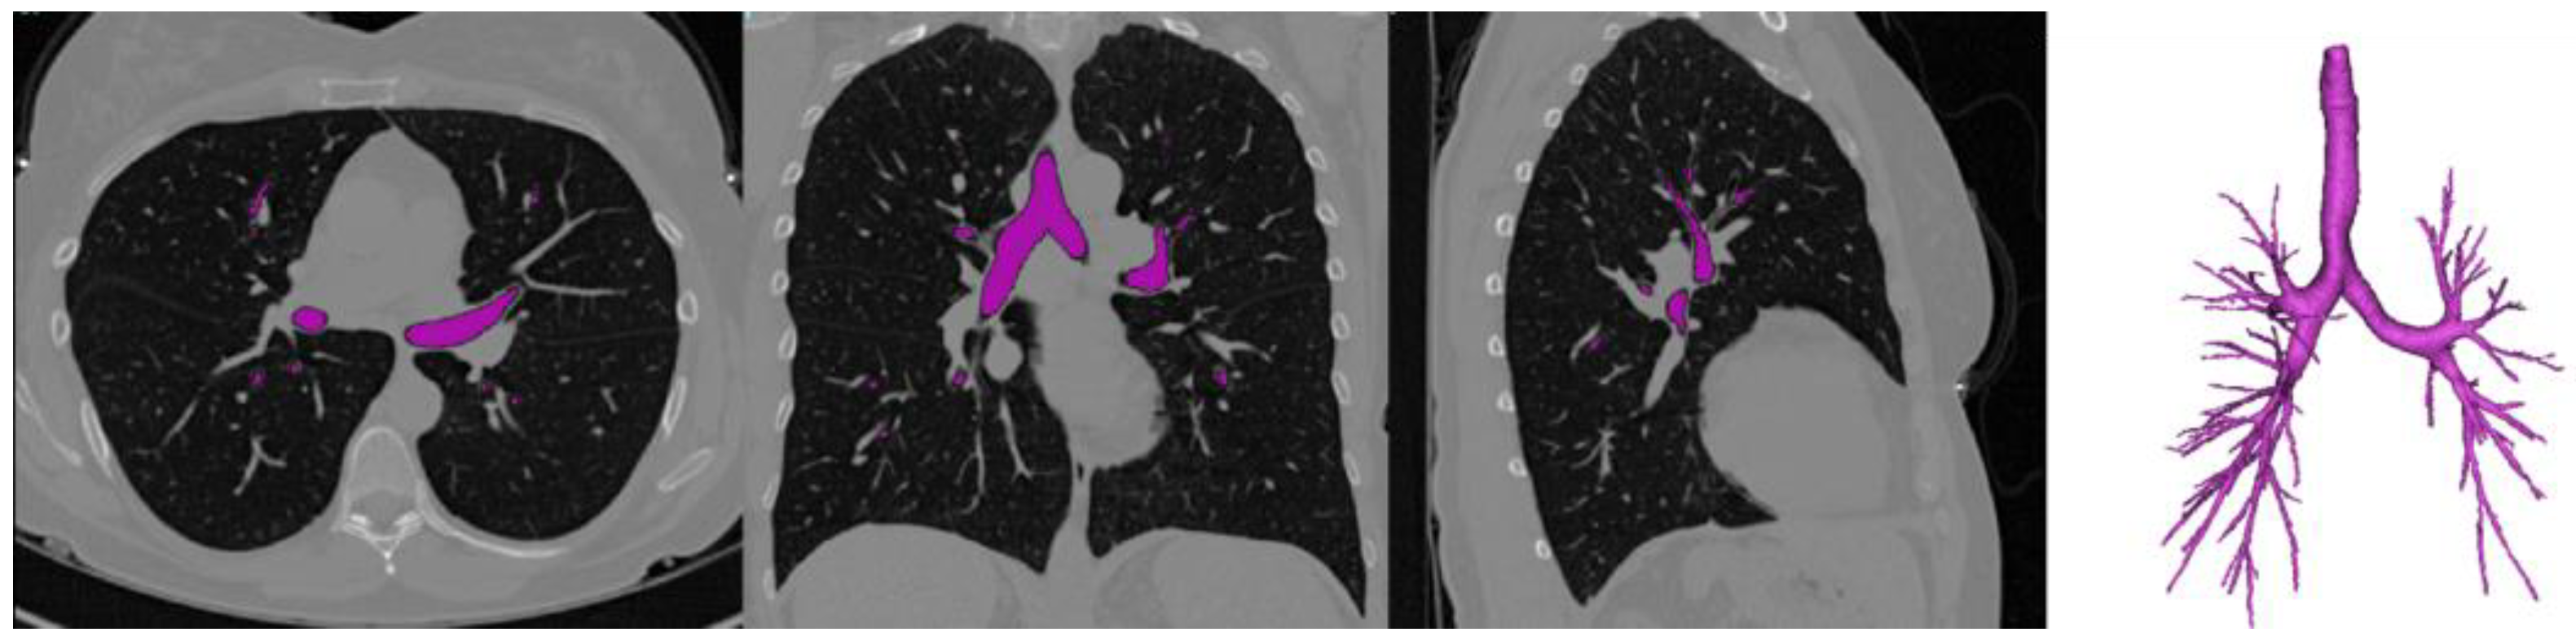

3.2.1. Airway Segmentation

CT Imaging

Segmentation of Pathological Bronchial Trees